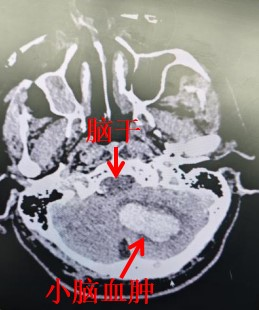

该患者为68岁男性,因突发剧烈头痛、眩晕呕吐并昏迷,被紧急送往第三师总医院救治。头颅CT检查显示:左侧小脑半球及蚓部出血量约15ml,脑干和第四脑室受压,伴梗阻性脑积水。神经外科特聘主任尹延庆副主任医师(援疆)、第一主任谢志强主任医师(援疆)带领孟庆阳医师、周烁医师组成的手术团队迅速对患者病情进行全面评估,考虑小脑出血易直接压迫脑干,导致呼吸、心跳骤停等严重后果,若不及时处理,患者随时有生命危险,随即决定采取“后颅窝小骨窗开颅小脑血肿清除术”对患者进行救治,并在麻醉科、重症医学科等多学科紧密协作下,制定了详细的手术及围术期管理方案,全力保障患者生命安全。